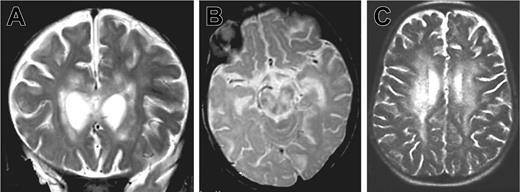

Patient 1 was the third child of consanguineous parents from Algeria. There was no known family history of neurologic disease or early death. Three other siblings were healthy. The patient was hypotrophic at birth (weight 2300 g, length 47 cm, and head circumference 30 cm at 39 weeks gestation). Neurologic symptoms were first noted at 5 months of age after an acute and apparently benign upper respiratory infection: poor head control, tremor of extremities, and abnormal postural tone for age. The patient was hospitalized 2 months later because of the onset of seizures, status epilepticus, ataxia, and coma without fever. Within 2 weeks, the patient developed persistent myoclonus, pyramidal rigidity of lower limbs, right facial weakness, and impaired ocular movements. Two brain magnetic resonance imagings (MRIs) were performed 3 weeks apart at the age of 8 months. Large areas of white matter at periventricular, deep supratentorial, and cerebellar locations were hyperintense in relaxation time (T) 2-weighted and fluid-attenuated inversion recovery (FLAIR) images and hypointense on T1-weighted images and showed contrast enhancement after application of gadolinium (Figure 1A-B). There was also evidence of lesions in the corpus callosum and brain stem mostly in the tegmentum and the pons. No subcortical, cortical, or basal ganglia abnormalities were detected. Lesions were larger on the second MRI. In addition, a moderate degree of hepatosplenomegaly and a 5-cm right cervical mass were detected.

Brain magnetic resonance images of patients 1 and 2. MRIs show large white matter lesions in periventricular areas and brain stem. (A) Patient 1, 7 months, coronal T2 section. (B) Patient 1, 7 months, sagittal T2 section. (C) Patient 2, 33 months, sagittal T2 section.

Three months later (33 months of age), patient 2 was admitted to our hospital with fever, weight loss, and anorexia. Clinical examination revealed massive hepatosplenomegaly. The results of laboratory investigations are shown in Table 1. Severe pancytopenia and a high percentage of HLA DR(+) CD4 and CD8 lymphocytes were observed. In addition, hypertriglyceridemia, hyponatremia, and lymphocytic meningitis were found. Transaminase, fibrinogen, and ferritin levels remained normal. Hemophagocytosis was observed on a bone marrow aspirate. Infection by herpes simplex viruses (HSVA-C), human herpes virus 6 (HHV6), cytomegalovirus (CMV), human immunodeficiency virus (HIV), adenovirus, bacteria, and fungi were excluded. Low copy number of EBV (0.8 log) was detected by PCR in the blood. CSF cultures were negative for bacteria and fungi. A normal level of interferon α (IFN-α; < 2 IU) was detected in the CSF, making viral infection highly unlikely. CSF lactate level was elevated. Treatment consisted of steroids and cyclosporine A (CsA). In 6 days, the hepatosplenomegaly, fever, and biomarkers of disease activity completely regressed, but on the seventh day, an acute neurologic deterioration occurred with coma and choreoathetoid movements. An MRI was performed, showing an extension of the lesions (Figure 1C).